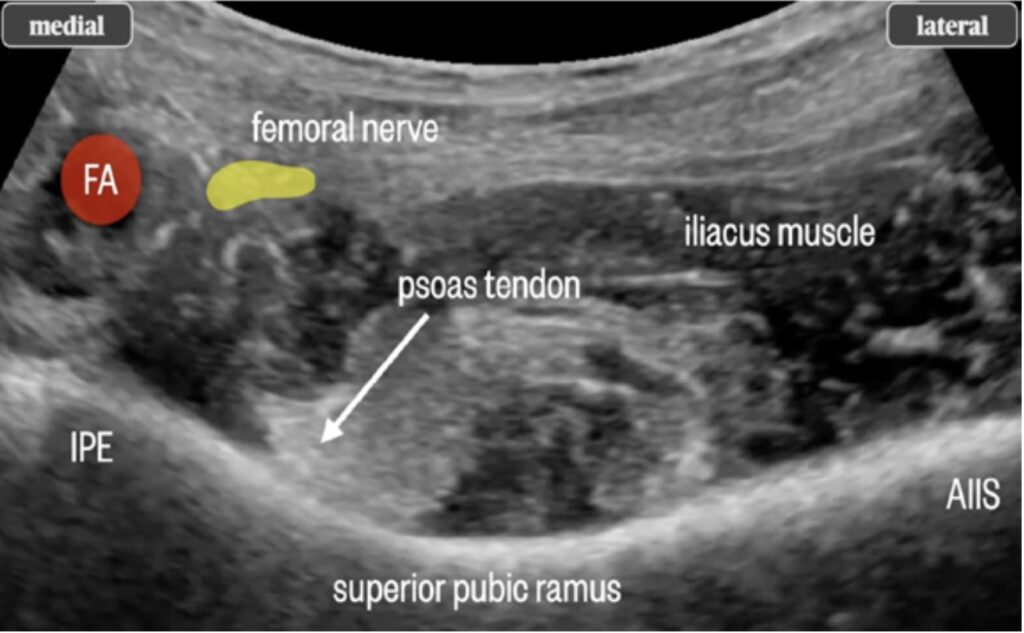

Figure 6. Close-up ultrasound image of anatomy relevant to PENG block. AIIS, anterior inferior iliac spine; IPE, iliopubic eminence; FA, femoral artery.

- Using either a linear or curved transducer, place the ultrasound probe over the anterior superior iliac spine, then move the probe medially to find the anterior inferior iliac spine and psoas muscle. For larger patients, the curvilinear probe often affords better visualization.

- Advance the needle under direct visualization to the psoas muscle. Use an in-plane approach, moving from lateral to medial until contact with the ilium is made under the psoas tendon (figures 3,4,5).